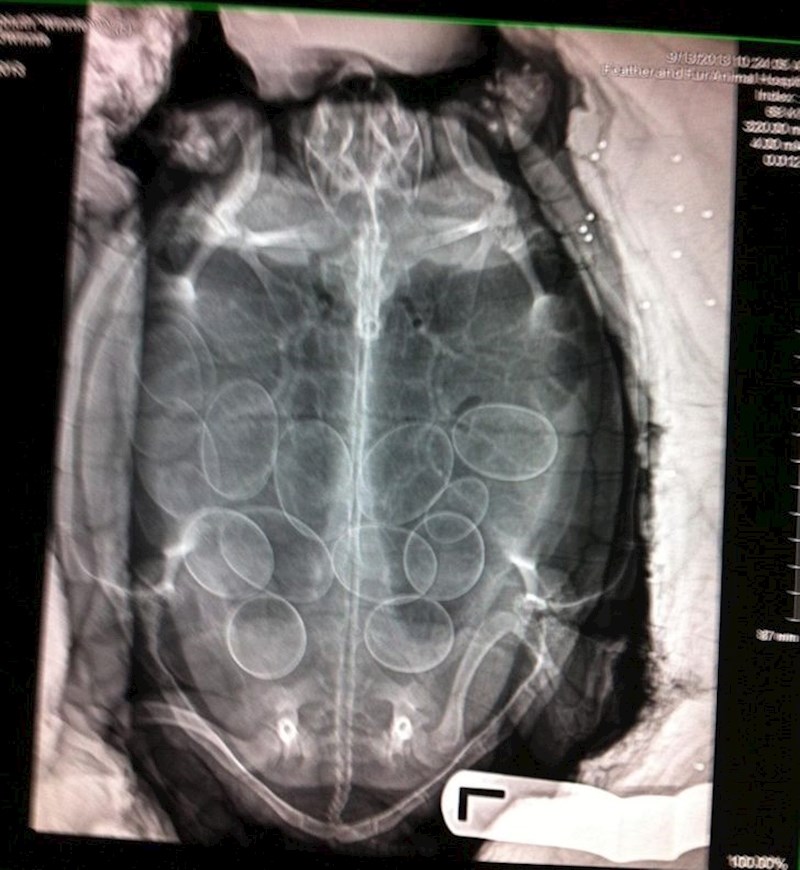

Kornjača